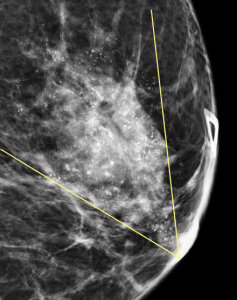

A spot magnification view in the ML projection is obtained:

How do you describe the distribution and morphology of the calcifications?

C. Segmental distribution; Coarse heterogeneous morphology

Explanation: These calcifications are in a segmental distribution, which is a roughly triangular shape which points towards the nipple. This pattern suggests that the calcifications are primarily located within the breast’s ductal system. The individual calcifications predominantly have discrete irregular shapes, are slightly coalescent, and are slightly larger than the fine pleomorphic type of calcification.